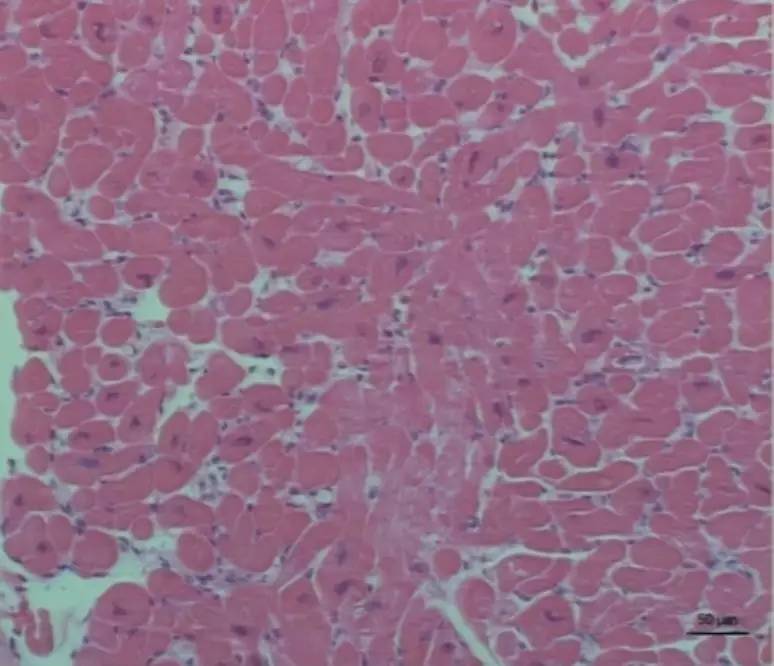

2016年5月26日,在局麻下行心内膜心肌活检,1周后病理结果回报提示:心内膜无增厚,心肌细胞肥大,极向略紊乱,心肌间质少量纤维性增生,以上形态学表现考虑肥厚型心肌病可能(因活检取材部位局限、组织量少、形态学诊断需结合临床)(图11)(图12)。

图11

图12

心肌活检虽然有部分肥厚型心肌病的特点,但是结合临床:(1)室壁厚度正常;(2)经积极抗心衰治疗后可平卧但右心衰仍非常明显,表现为仍有下肢水肿,颈静脉怒张--左右心不平行;(3)房颤病史时间较长;(4)双房大尤其但是右房增大,右心导管检查证实肺动脉高压,合并二尖瓣脱垂、关闭不全;(5)右心导管检查符合心室限制型病理生理特征:心室充盈时,心肌僵硬度增高或顺应性降低,而导致心室压力迅速上升,而心室容量只有不成比例的少许增加。基于此,请示上级医师,最终诊断:(1)限制型心肌病,心脏扩大,肺动脉高压;(2)心律失常,永久性房颤;(3)瓣膜性心脏病,二尖瓣脱垂,二尖瓣中重度关闭不全;(4)先心病,房间隔缺损(Ⅱ孔多发型)。